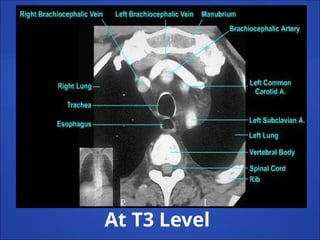

At T3 Level